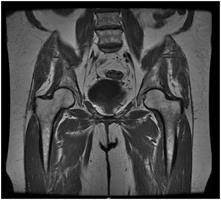

Pelvis MRI

An MRI of the pelvis can help find problems such as tumours in the ovaries, uterus, prostate, rectum, and anus. It also can be used to look for an anal fistula (a tube-shaped passage from the anal canal to a hole in the skin near the anus) and look for the cause of pelvic pain in women, such as endometriosis.